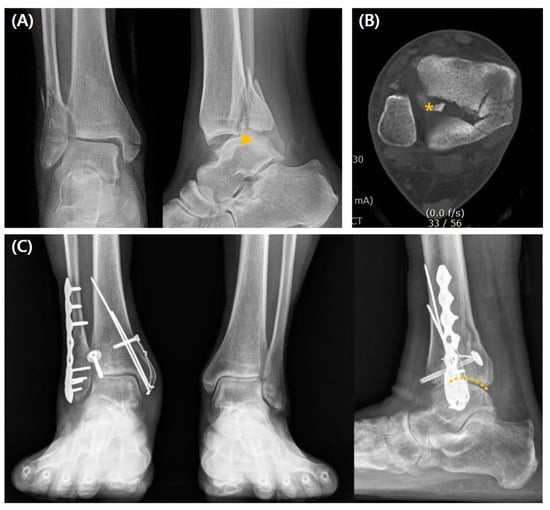

3.2. Comparison Between the Fixation and Non-Fixation Groups Within Type 2 Fracture

The rates of poor reduction assessed by the CT, postoperative step-off, and PTOA development were significantly higher in the non-fixation group (all, p < 0.001). All the measured clinical values were statistically superior for the fixation group (p < 0.001). Although not statistically significant, there was a trend toward a higher complication rate in the fixation group (42.1% vs. 34.8%, p = 0.366) (Table 2). A radiographic case example of a type 2 fracture is depicted in Figure 4.

A logistic regression analysis was performed on variables showing significant differences between the surgical fixation and non-fixation groups in Table 3 to analyze the factors influencing the decision for surgical fixation of posterior malleolar fractures that predict favorable treatment outcomes. The dependent variable was defined based on an AOFAS score threshold of 90. Independent variables included in the regression model were those that demonstrated statistically significant differences according to the surgical fixation status of the posterior malleolar fracture. These variables comprised quality of reduction by CT, step-off, and PTOA. Additionally, basic demographic data, including age, sex, and BMI, were incorporated as independent variables. Among the postoperative factors determined by the surgical fixation status of posterior malleolar fractures, PTOA [odds ratio = 6.212 (1.275 to 30.270), p = 0.024] and step-off [18.945 (3.942 to 91.044), p < 0.001] were observed to influence functional treatment outcomes (Table 3). This suggests that for type 2 posterior malleolar fractures, where significant preoperative articular displacement is observed, considering surgical fixation may contribute to predicting favorable treatment outcomes.

In type 2 PMF, more favorable radiological and clinical outcomes were obtained by the fixation group than the non-fixation group. Our findings agreed with previous studies that demonstrated the efficiency of the direct approach and internal fixation in terms of articular congruity restoration and improved functional outcomes. This type of PMF that involves the anterior portion of the medial malleolus usually shows comminuted fragments and more ICF that warrant surgical reduction and fixation [6,12,26,27,29,32,35,40,41,42]. However, considering the higher rate of hallux flexion deficit or metalwork irritation in plate osteosynthesis, posterior screw osteosynthesis could be considered for better clinical results [11,21]. There are few studies comparing the direct reduction and screw-versus-plate fixation of PMF. In a prospective comparative study of posterior screw and plate fixations through the posterolateral approach with a follow-up of approximately 3 years, Erdem et al. [43] obtained satisfactory and equivalent radiological and functional outcomes for both groups.

Figure 4. A case of a 44-year-old woman who underwent a direct approach and posterior screw fixation for type 2 PMF. (A) Preoperative radiographs show comminuted fracture (arrow), and (B) preoperative CT scan images show a posterior malleolar fragment representing type 2 fracture with the ICF (asterisk) and step-off. (C) Weight-bearing radiographs obtained 3 years postoperatively show good reduction without the development of PTOA (dotted line; anatomically reduced joint surface).